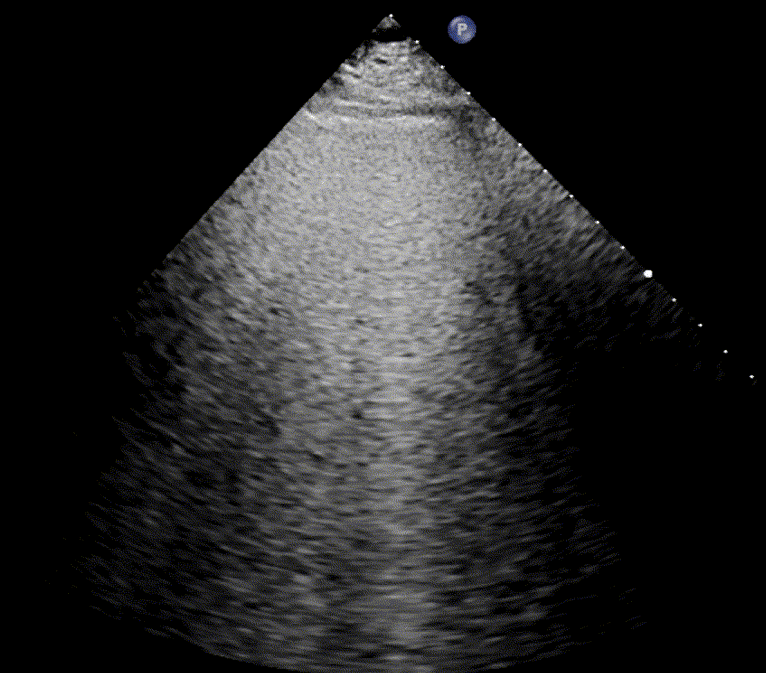

In healthy, air-filled lungs, the ultrasound image appears gray. This occurs because air scatters sound waves as they encounter solid interfaces such as the pleura, resulting in a diffuse, speckled gray appearance beneath it. Within normal lung parenchyma, there is minimal acoustic impedance mismatch to reflect the ultrasound beam; instead, the beam is absorbed by air within the alveoli. Consequently, in a normal lung ultrasound, the parenchymal texture is not visualized. The only visible structure is the pleural line — a bright, horizontal echo that moves synchronously with respiration.

A-lines

A-lines are highly echogenic, horizontal reverberation artifacts that appear parallel to and equidistant beneath the pleural line. They result from repetitive reflection of the ultrasound beam between the pleura and the probe, producing regularly spaced bright lines on the image.

The presence of A-lines indicates a normally aerated, air-filled lung. They are typically observed when imaging at a depth of 9–11 cm, and are most distinct when the ultrasound beam is perpendicular to the pleural surface.

A-lines may also be seen in cases of pneumothorax, as air trapped at the parietal pleura similarly reflects ultrasound waves. The key distinguishing feature is the absence of lung sliding in pneumothorax, which differentiates pathological from physiological A-lines.